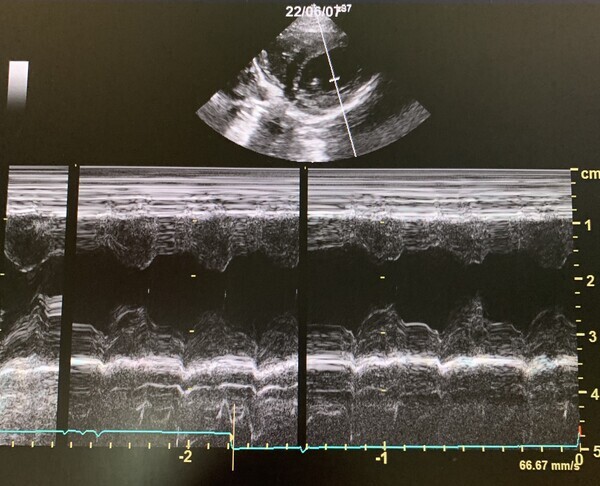

心臓病の検査で特に大きな要となるのが、超音波検査でありますが、大変高い技術が求められる検査であります。この技術により診断が左右することも大いにあります。当院では幅広い知識と高い技術で検査を行い、診断しております。この検査では、動物に横になったり、仰向けになったりしてもらいますが、その姿勢が苦手な子、またその姿勢によって息苦しくなってしまう子に対しては、立ったままの姿勢での検査を行っております。